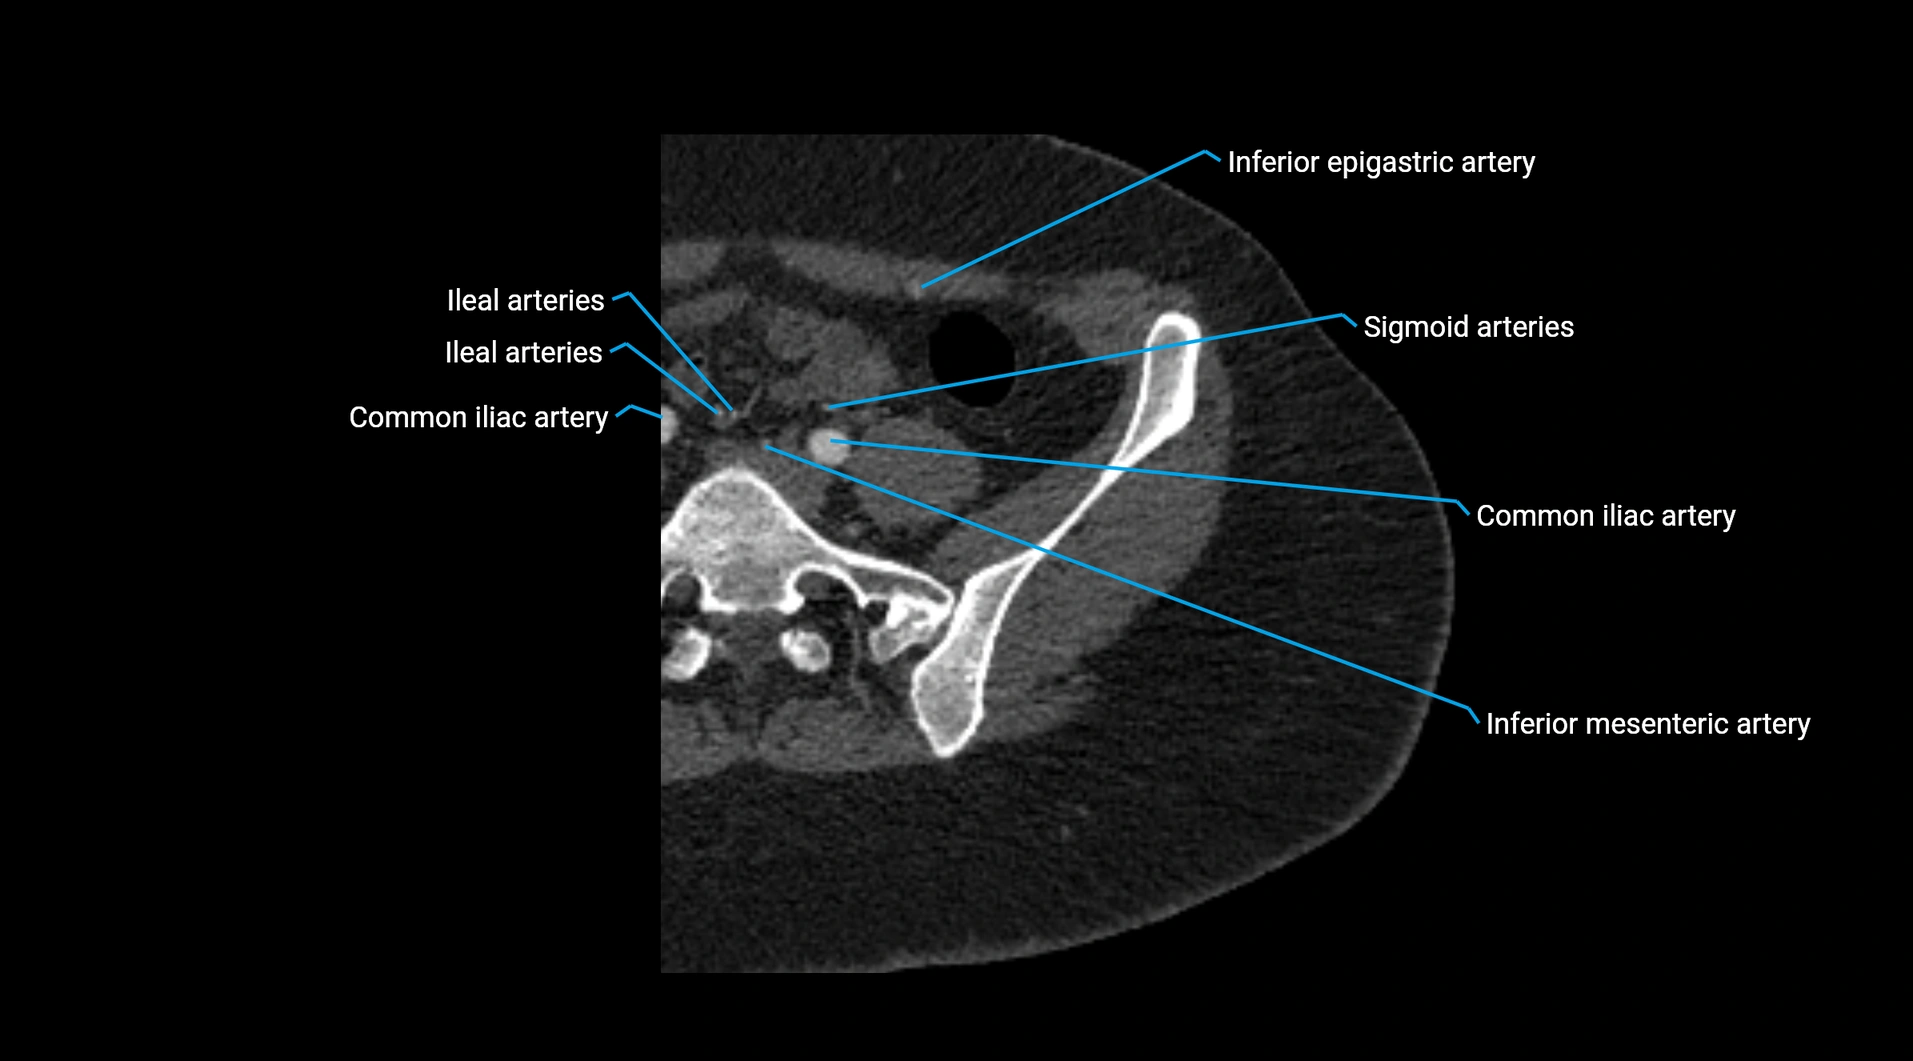

Contrast-enhanced CT (CTA):

• Gold standard for abdominal aortic imaging

• Provides excellent detail of lumen, wall, aneurysm, thrombus, and branch vessels

• Multiplanar and 3D reconstructions help in aneurysm measurement, stent graft planning, and dissection evaluation

• Detects acute rupture, traumatic injury, or occlusion with high sensitivity